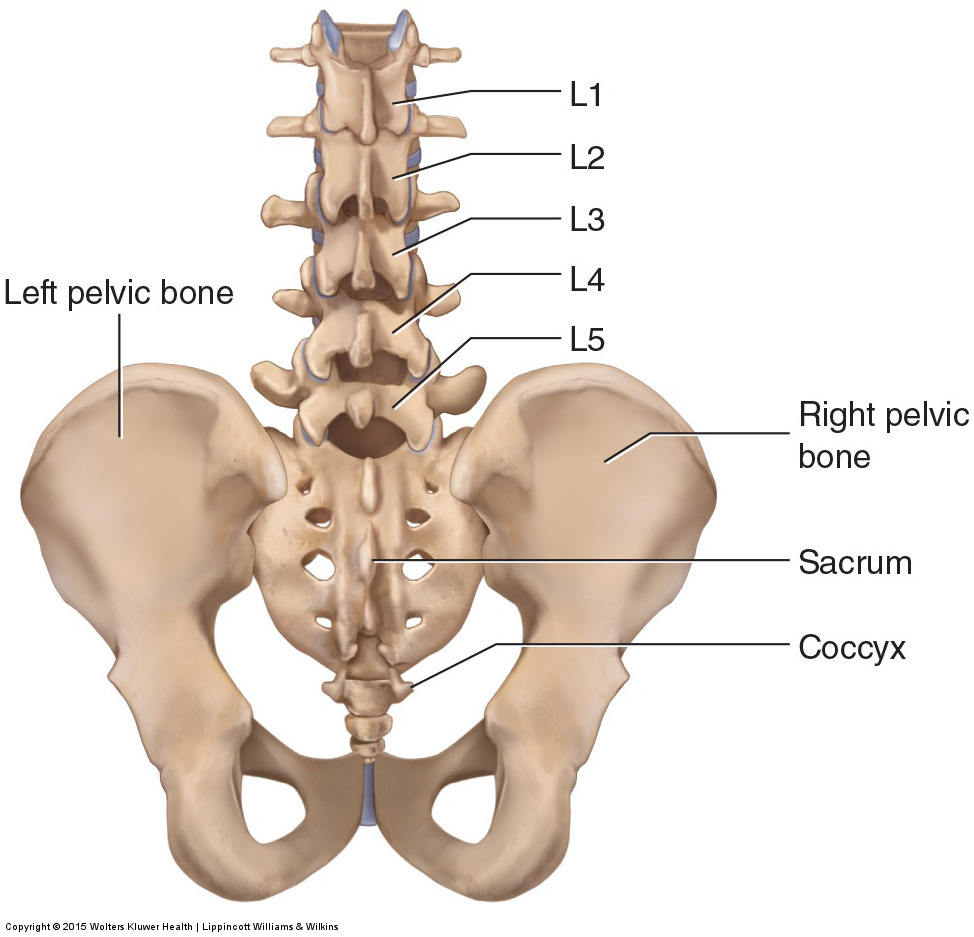

The lumbar spine with the segments representing L1, L2 … L5 vertebras …

Anatomy of the Lumbar Spine – TrialExhibits Inc.

Learn all about lumbar spine anatomy from a world-renowned Spine Expert …

Human Spine With Pelvis and Sacrum Structure model 3D model | CGTrader

spine l2 l3 l4 l5